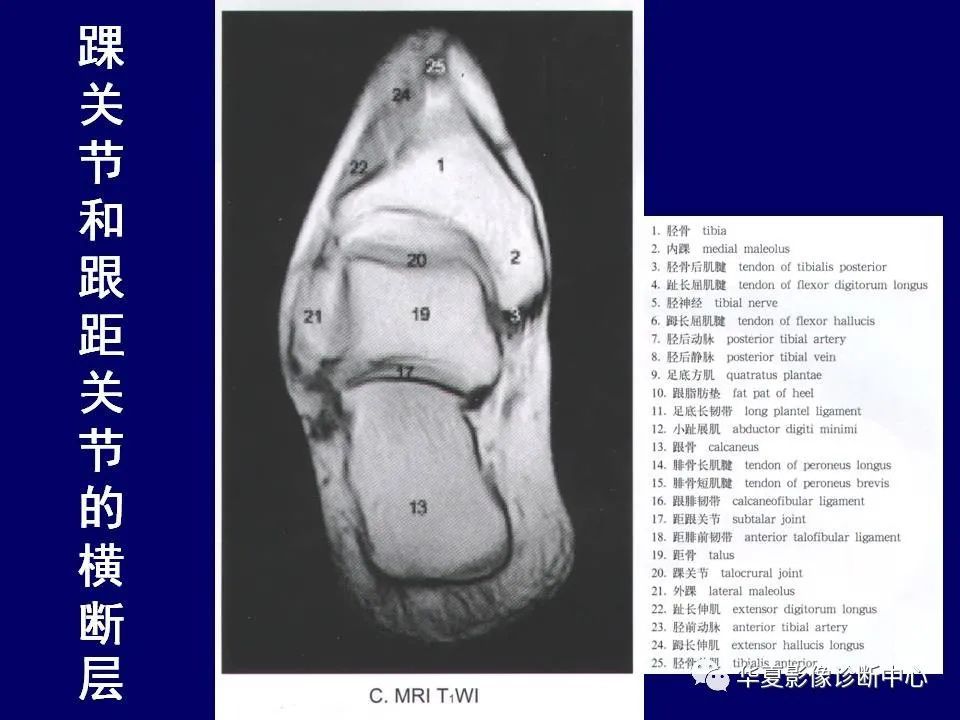

正常踝关节mr解剖ppt

图片尺寸1080x810